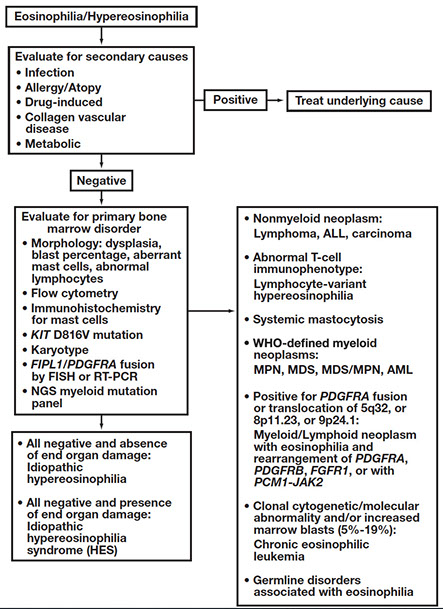

Eosinophilia

_____________________________________

• Group of disorders marked by sustained overproduction of eosinophils

• Eosinophilic infiltration and release of mediators may cause damage to multiple organs

• Variable cytologic features

Numerous causes, both neoplastic and non-neoplastic

• Broad workup can be daunting

• Methodical algorithmic approach

– Manage ancillary testing

– Ensure thorough, appropriate workup

– Diagnose/exclude specific disease entities

Approach to Eosinophilia

• Systematically collect data!

• Exclude secondary causes

• Assess for a primary clonal disorder

– Specific treatments for certain diseases (eg, TKI in CML, PDGFRA-rearranged)

• Idiopathic HE/HES is a diagnosis of exclusion

- Can be fairly overwhelming as to how and where to begin